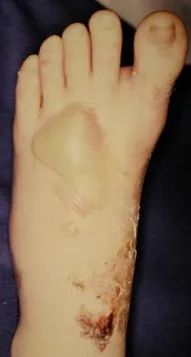

中足疼痛、负重困难;足背肿胀;由于可能的自行复位可致畸形多变。

足底瘀青可出现较晚;跖跗关节局部压痛;轻度跖屈、背伸和旋转应力可显示不稳。

血管神经检查:足背动脉、腓深神经 预防骨筋膜室综合症

如果不能在伤后6-8小时手术,应耐心等待,待患足肿胀消退出现褶皱时再行手术治疗。若冒然进行手术,可能会加重术后肿胀,或者皮肤不愈合以及皮瓣因压力过大而坏死。

切开复位内固定急诊手术指征:开放性骨折;血管神经损伤(足背动脉);骨筋膜室综合症。

并发症:创伤性关节炎、骨筋膜室综合症、感染、血管神经损伤、内固定失败、疼痛。